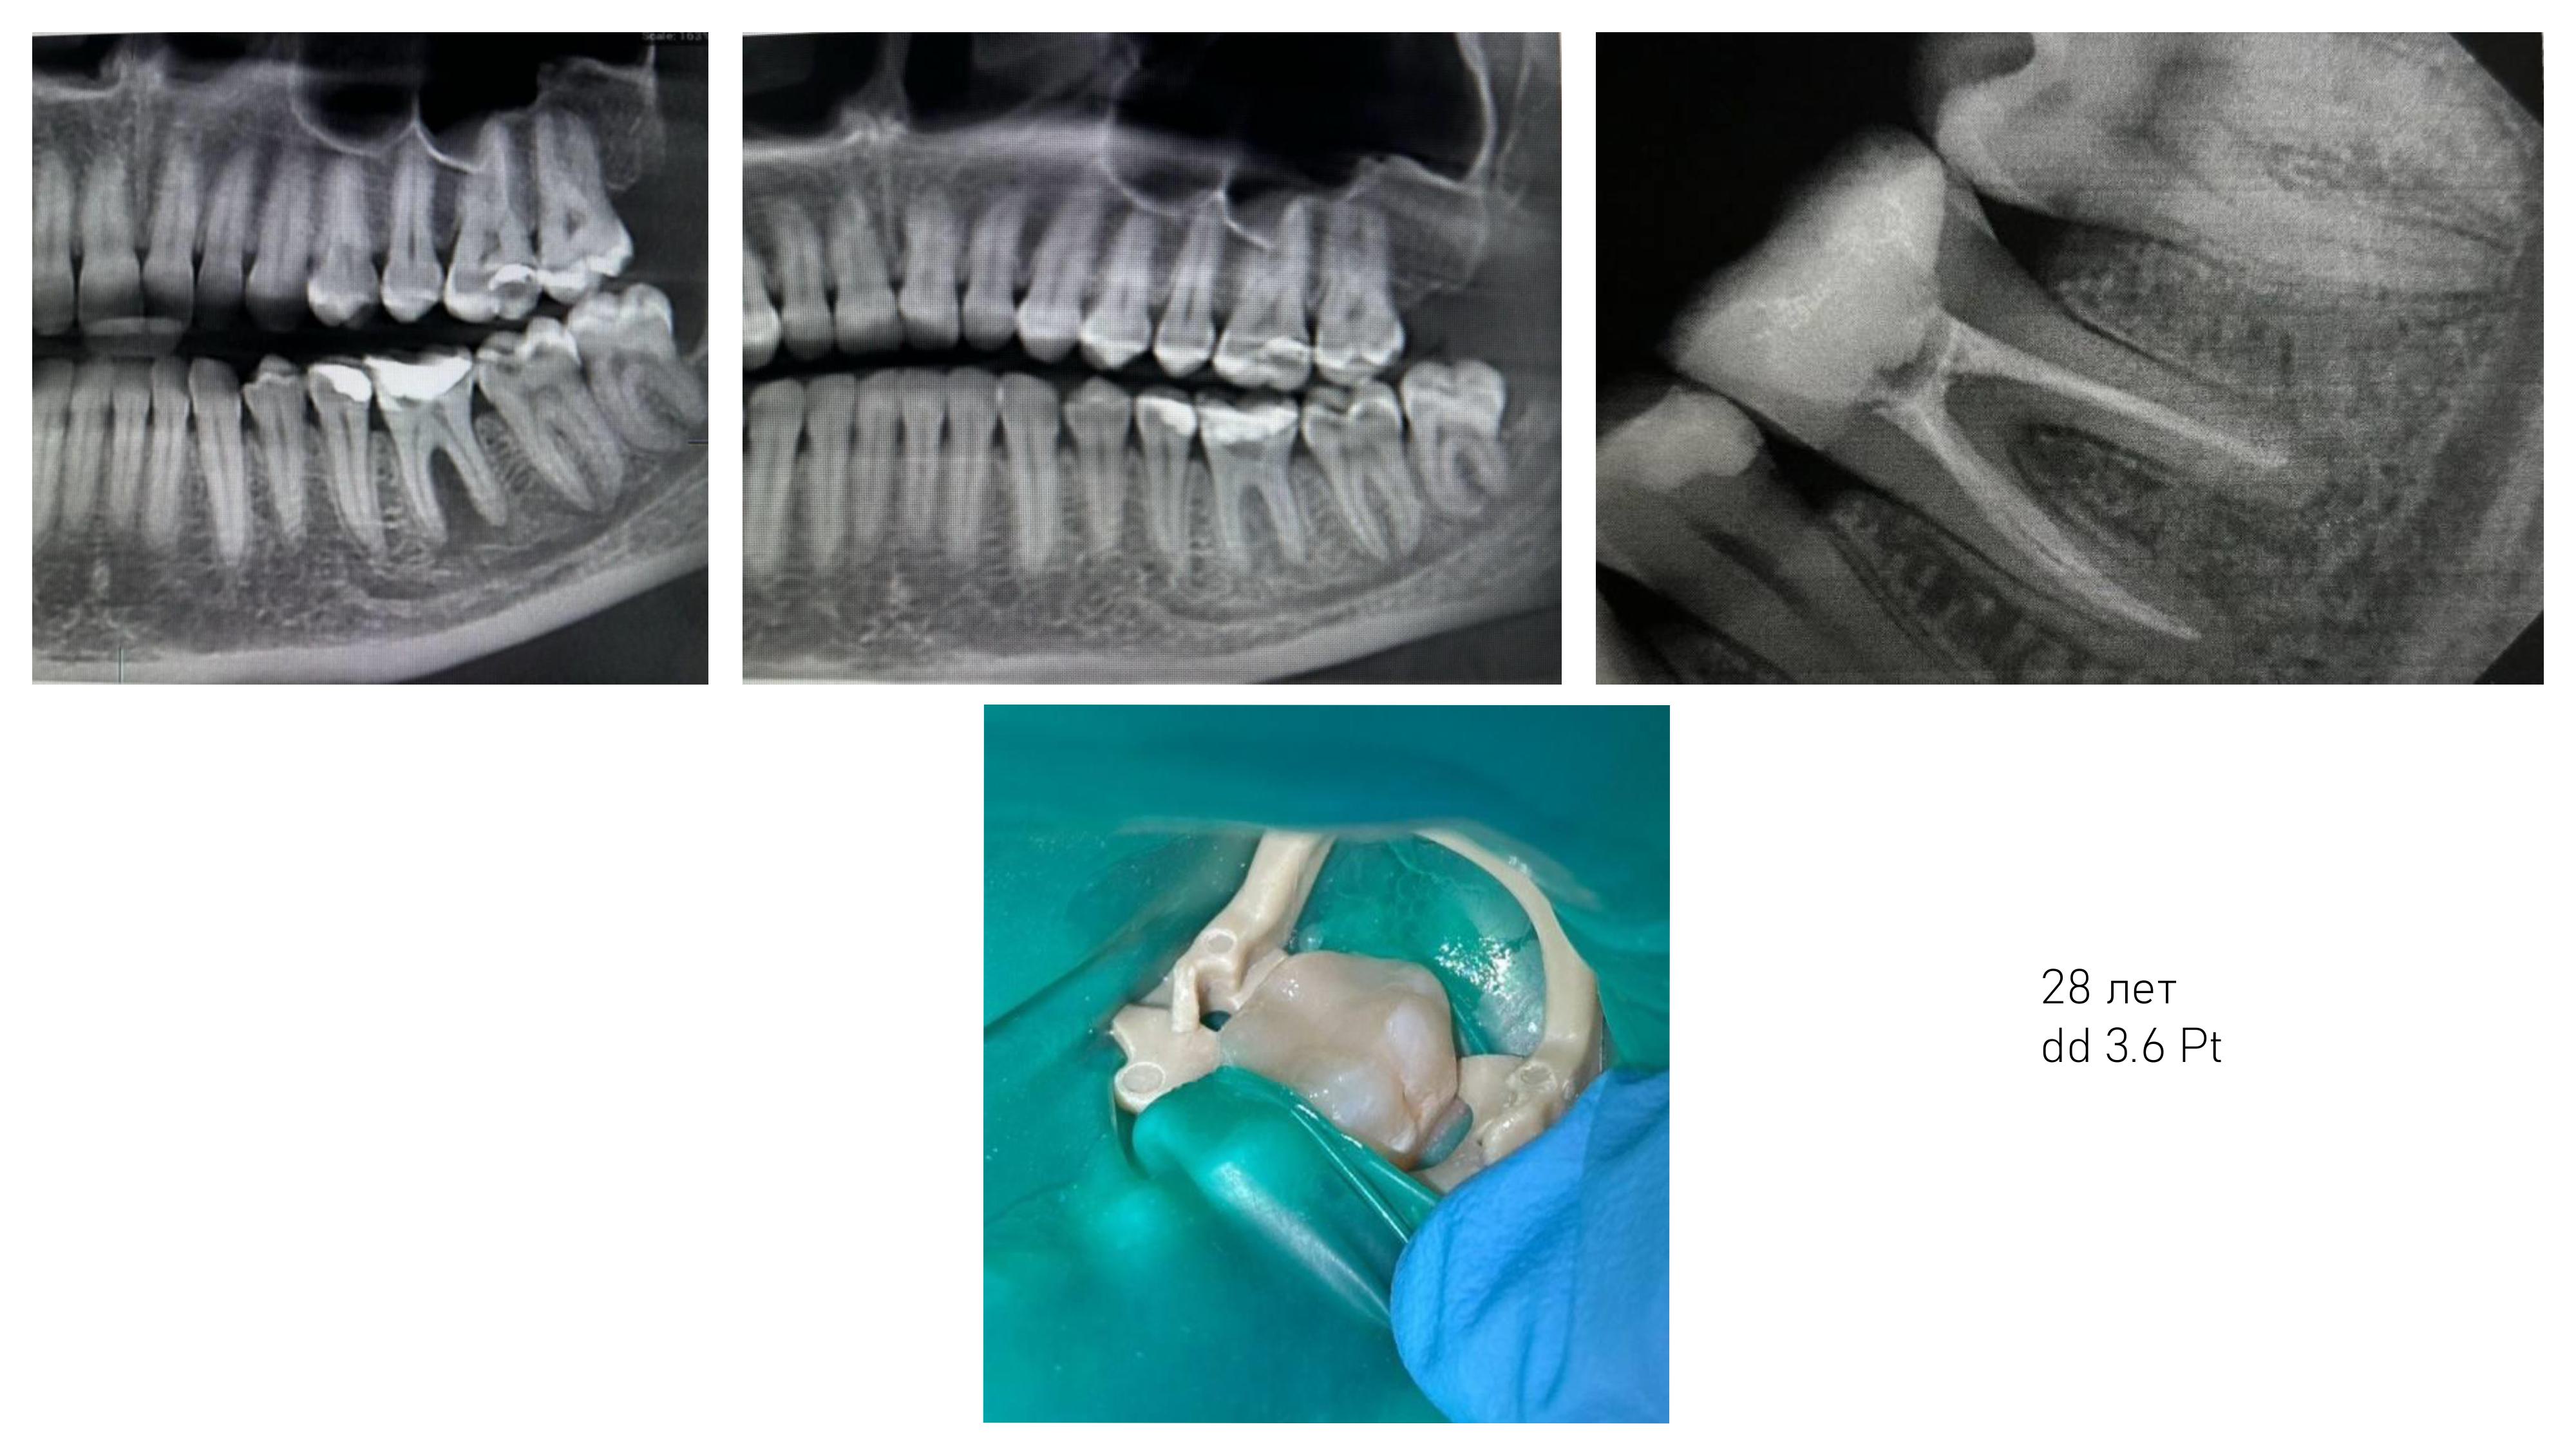

6. Диагностика и лечение кариеса временных и постоянных зубов с использованием микроскопа, лечение пульпитов и периодонтитов временных и постоянных зубов.

7. Подготовка зубов к ортопедическому и ортодонтическому лечению, с учетом назначенного плана лечения